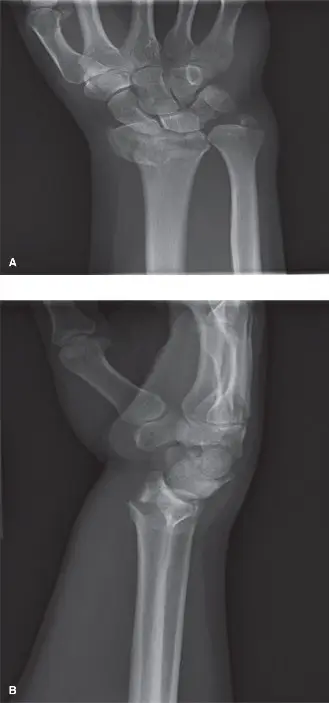

• الأشعة السينية (X-rays): تُعد الخطوة الأولى والأساسية. تُؤخذ صور متعددة للرسغ من زوايا مختلفة (أمامية خلفية، جانبية، مائلة) لتحديد موقع الكسر، نوعه، درجة الإزاحة، ووجود أي تفتت.

تُصنف كسور الكعبرة البعيدة المعقدة داخل المفصل بناءً على عدة عوامل، بما في ذلك مدى تفتت العظم، ودرجة الإزاحة، وعدد القطع العظمية المتضمنة، ومدى تأثيرها على السطح المفصلي. بعض التصنيفات الشائعة تشمل:

• كسور كوليس (Colles' Fracture): الأكثر شيوعًا، ويتميز بإزاحة الجزء البعيد من الكعبرة للخلف (dorsal displacement).

• كسور سميث (Smith's Fracture): إزاحة الجزء البعيد من الكعبرة للأمام (volar displacement).

• كسور بارتون (Barton's Fracture): كسر مائل داخل المفصل مع خلع جزئي للرسغ.

• كسور ذات تفتت شديد (Highly Comminuted Fractures): يتفتت العظم إلى عدة قطع صغيرة، مما يجعل إعادة بناءه تحديًا.

• كسور مفتوحة (Open Fractures): حيث تخترق العظام الجلد، مما يزيد من خطر العدوى ويتطلب تدخلًا عاجلاً.

تتطلب الكسور المعقدة داخل المفصل تقييمًا دقيقًا باستخدام الأشعة السينية والتصوير المقطعي المحوسب (CT Scan) لتحديد مدى الضرر بدقة والتخطيط للعلاج الأمثل.